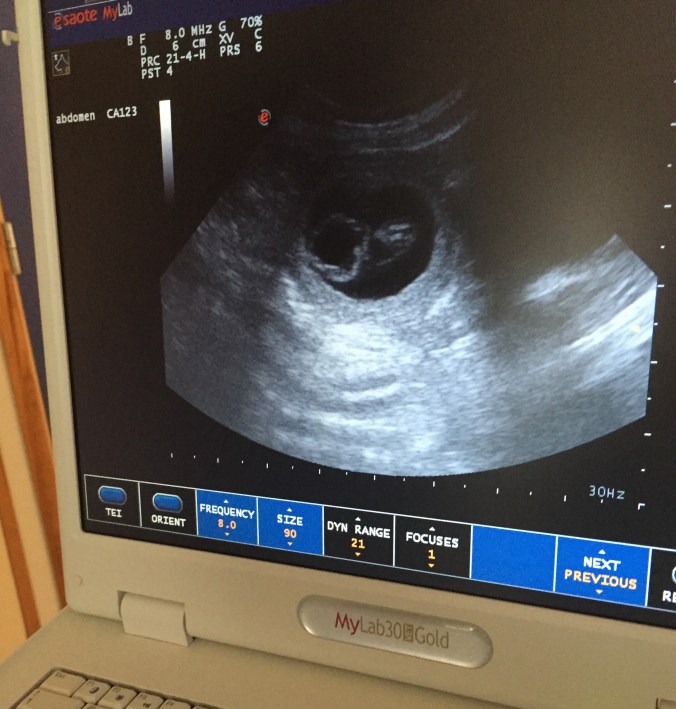

På mandag var Bonnie til dyrlegen på ultralyd. Kor mange kvelpar ho har er litt vanskeleg å seie, men at det er fleire liv i magen er heilt sikkert. Hunden har vore noko slapp siste tida med lite matlyst, og har også kasta opp ein gong.

Dyrlege Gunnar meiner at den beste måten å telje kvalpar på er ved å kjenne på magen til hunden